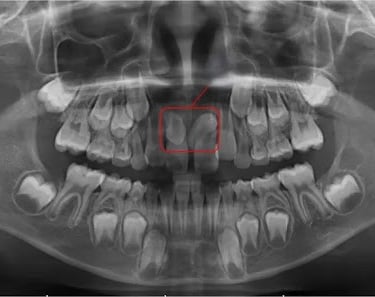

Dientes Supernumerarios

Los dientes supernumerarios son dientes adicionales que pueden aparecer en la boca y causar problemas de alineación o erupción de otros dientes.

Los pacientes pueden notar dientes adicionales en la boca, lo que puede causar apiñamiento o problemas estéticos.

El tratamiento incluye la extracción quirúrgica de los dientes supernumerarios.